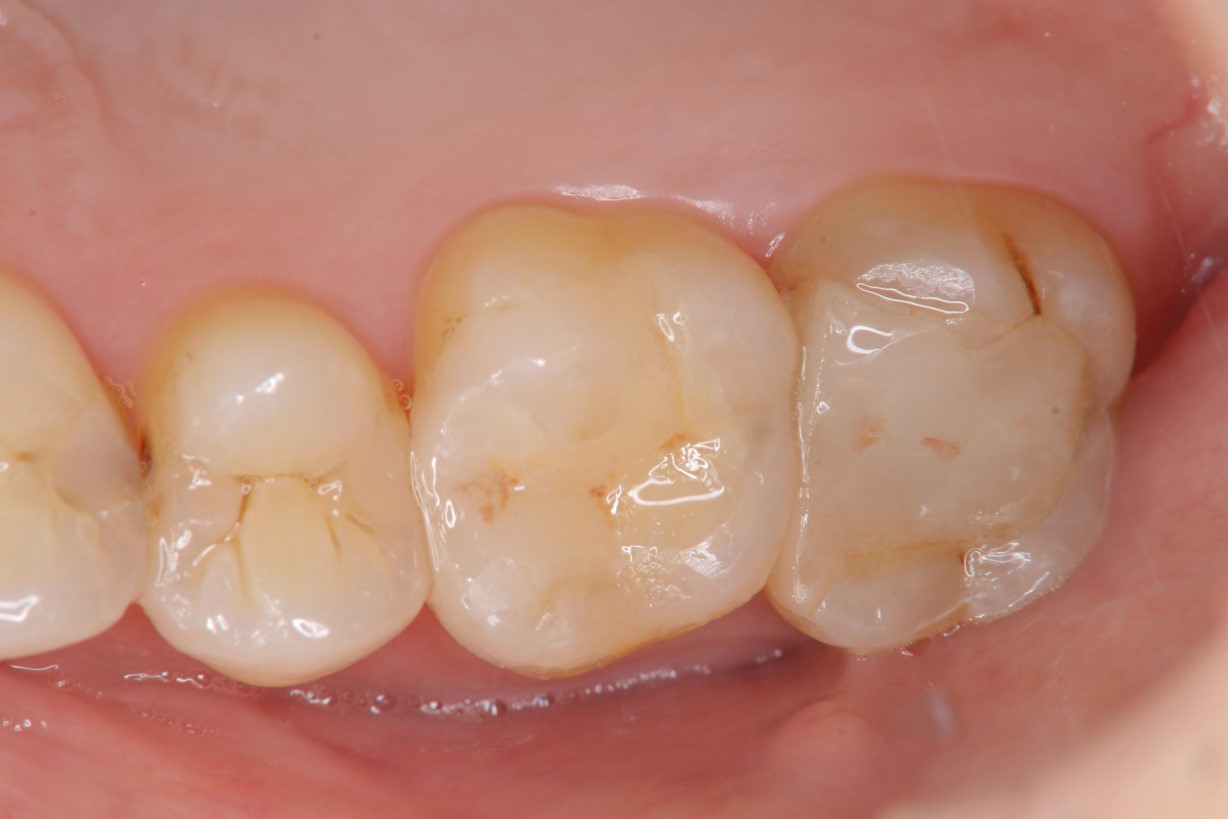

治療後,患者適應良好

術前、術後比較